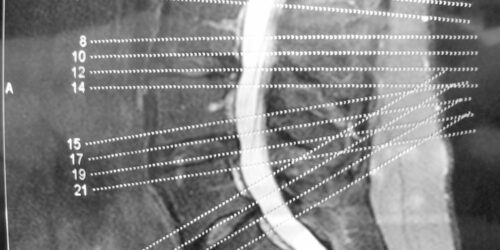

When you mention the term degenerative disease, it refers to the gradual deterioration of the body tissues or cells over the years due to the natural aging process. As we age, our spine starts giving in to the stress of providing flexibility and support to our back. The components of the spine start deteriorating slowly, and you will experience back pain and stiffness in the spine.

Bulging disc is a degenerative disc disease that is caused by one of the discs in the spinal vertebrae (often in the lower back) becomes weakened and swollen through a spinal crevice and the disc moves from its usual position. This happens over time without any associated pain. As the problem aggravates, the bulging disc affects the surrounding nerves.

Both degenerative disc and joint diseases affect the spine of an individual. There comes a point in everyone’s life where their spine starts getting excessively strained due to the lifelong stress and pressure it endures. This does not happen suddenly; it is a slow, gradual deterioration and wearing of the tissues that causes these spinal conditions.

A degenerative disc disease, bulging disc affects people in their older age. With age, the discs in the spine become weak as the water content deteriorates. The discs become vulnerable to complications such as bulges. Bad posture, sedentary lifestyle, an injury and occupational hazards such as heavy lifting, bending, standing and driving for long hours can bring about bulging disc.